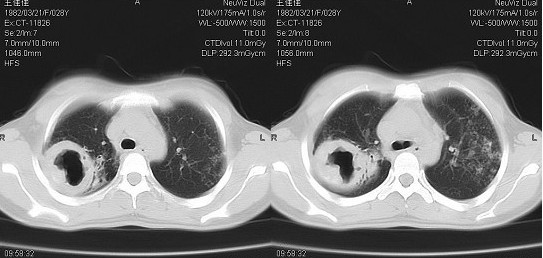

影像学特点[编辑 | 编辑源代码]

表现复杂多样,有以下特点:

- 肺部同时可有渗出、干酪、纤维、空洞、胸膜增厚、钙化等不同病期的病变。空洞多在一侧或两侧上中肺野,可单发或多单发,空洞的壁被较厚的纤维组织所包围,空洞周围的肺组织多伴有进行性支气管播散病灶和纤维修补同时存在,并常以纤维增生为主。

- 患侧肋间隙变窄,纵膈、气管阴影向患侧移位。

- 患侧肺门上提,肺纹理呈垂柳状,膈肌上升。

- 对侧肺呈代偿性肺气肿,心影变小呈滴状心,膈肌下降。

- 有支气管播散病灶、胸膜增厚粘连,膈肌可呈幕状。

- CT可见到明显的支气管扩张、肺纤维化、肺气肿、肺不张等表现。